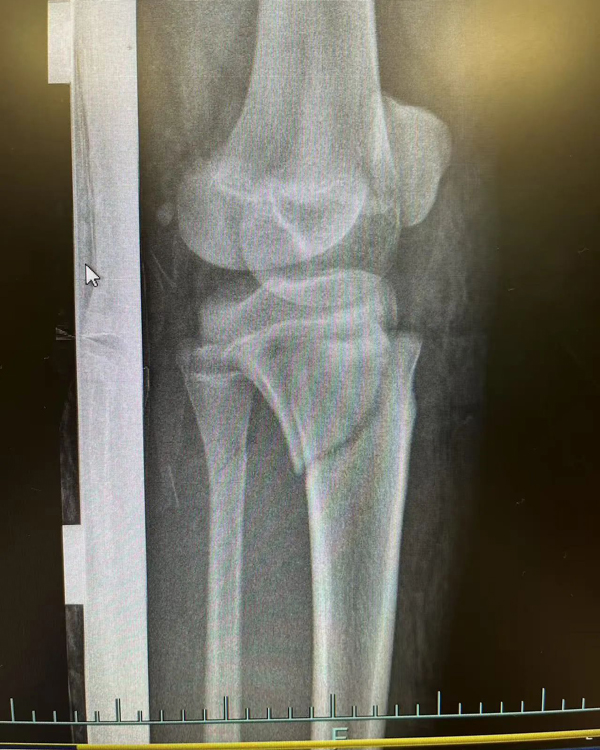

复位前

复位后

进修期间,一段特殊的经历让李刚感触颇深。2月底,一名女性患者因摔伤致左前臂肿痛伴活动受限被送入富阳骨伤医院。通过交流,李刚发现患者竟是家乡同胞,立即用方言安抚其情绪,这位老乡告诉李刚,自己在杭州工作,这次摔伤后先去了别的医院,给出的治疗方案是手术治疗,但听闻富阳中医骨伤医院的中医正骨技术后,慕名而来。经专家团队评估,最终为该患者采用“张氏骨伤疗法”中的手法复位结合杉树皮夹板外固定技术,未开刀便成功修复骨折。